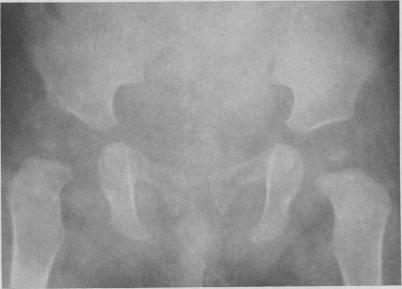

UNTREATED CONGENITAL HIP DISEASE. A STUDY OF THE EPIDEMIOLOGY, NATURAL HISTORY, AND SOCIAL ASPECTS OF THE DISEASE IN A NAVAJO POPULATION.

Am J Public Health Nations Health. 1965 Feb;55(Suppl 2):SUPPL:1-44.